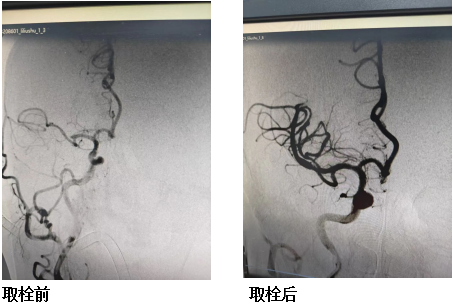

2月24日,罗先生因胸痛入院,次日清晨突发言语含糊、左侧肢体无力、口角歪斜等急性卒中症状。邹永周紧急会诊,凭借20年脑血管病临床经验,迅速判断为醒后致残性卒中,并与科主任江顺福一起快速判断考虑大血管病变,病情随时可能进一步恶化。医院立即启动卒中绿色通道,同步完成头颅MRI+MRA及CTP检查,结果显示:核心梗死面积极小、缺血半暗带面积大——这意味着,只要及时开通血管,行急诊经皮颅内动脉取栓术,大量脑组织还有救。

向家属清晰说明急诊经皮颅内动脉取栓术的必要性、流程与风险后。家属签字后,多学科联动机制立即运转:介入团队、麻醉师提前在介入室待命,原本串联的术前准备步骤被优化为并联操作——从家属签字、手术启动到手术结束,全程仅用35分钟,创下医院卒中救治的高效纪录。

急诊经皮颅内动脉取栓术成功打通右侧大脑中动脉闭塞段,患者术后即刻左上肢肌力恢复至3级、左下肢4级,言语清晰,复查头颅CT未见明显低密度灶。在神经内科精心诊疗与全程指导下,患者住院仅10余天即可自行行走,顺利出院。